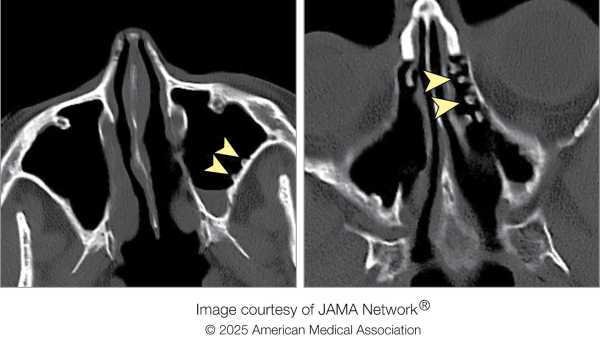

Що сталося далі: лікарі виміряли життєво важливі показники чоловіка, які не були чимось незвичайним. Вони також зробили комп’ютерну томографію його мозку, яка виявила численні кістоподібні ураження, розкидані по обох півкулях. Зокрема, ці нарости з’явилися в білій речовині органу, ізольованому дроті, що відходить від клітин мозку.

Пацієнта негайно госпіталізували для консультації нейрохірурга. МРТ підтвердила те, що було видно на КТ, але також виявила скупчення рідини навколо кіст у мозку чоловіка.

Діагноз: Запідозривши можливу паразитарну інфекцію, нейрохірургічне відділення направило пацієнта до спеціалістів з інфекційних захворювань, які провели низку аналізів. Один з аналізів показав, що кров чоловіка містила антитіла проти Taenia solium, стрічкового черв’яка, який зазвичай зустрічається у свиней, мешкаючи в їхньому кишечнику та м’язах і потрапляючи з фекаліями. У випадку чоловіка личинки черв’яка вторглися в його мозок і були впроваджені в кісти всередині тканини. Коли T. solium вражає нервову систему таким чином, цей стан називається нейроцистицеркозом.